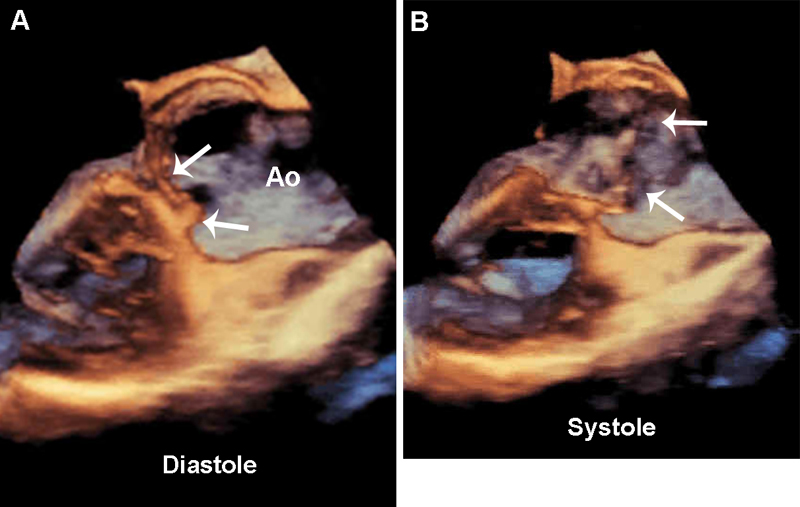

فحوصات تشخيصية لبعض امراض القلب والشرايين التاجية